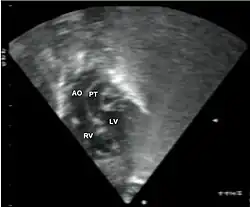

- Echocardiogram: An echocardiogram is an ultrasound of the heart that accurately assesses the heart’s structure and function, and can show the specific features of TGA, if present. This imaging modality allows for the definitive diagnosis of TGA to be made.[3]